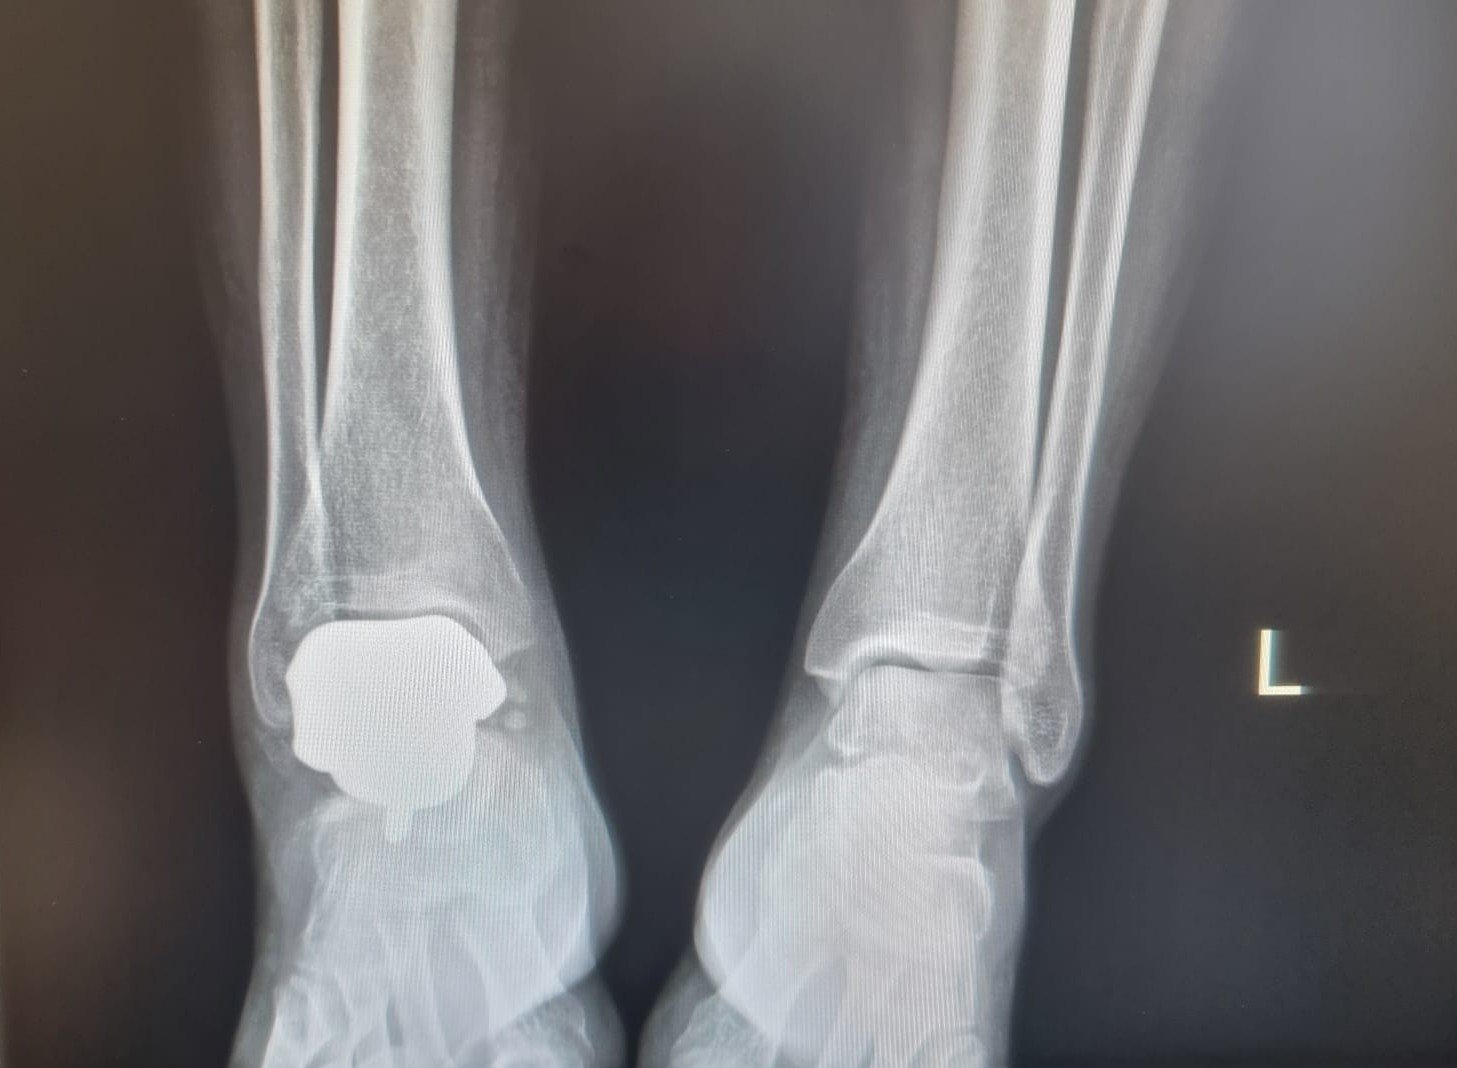

Téměř 1 rok po implantaci CM Talus

Custom-made talární náhrada poškozené kosti navržená na základě CT dat se zrcadlením zdravé strany.

Fixace spongiózními šrouby do calcanea, trabekulární struktura na kontaktním povrchu.